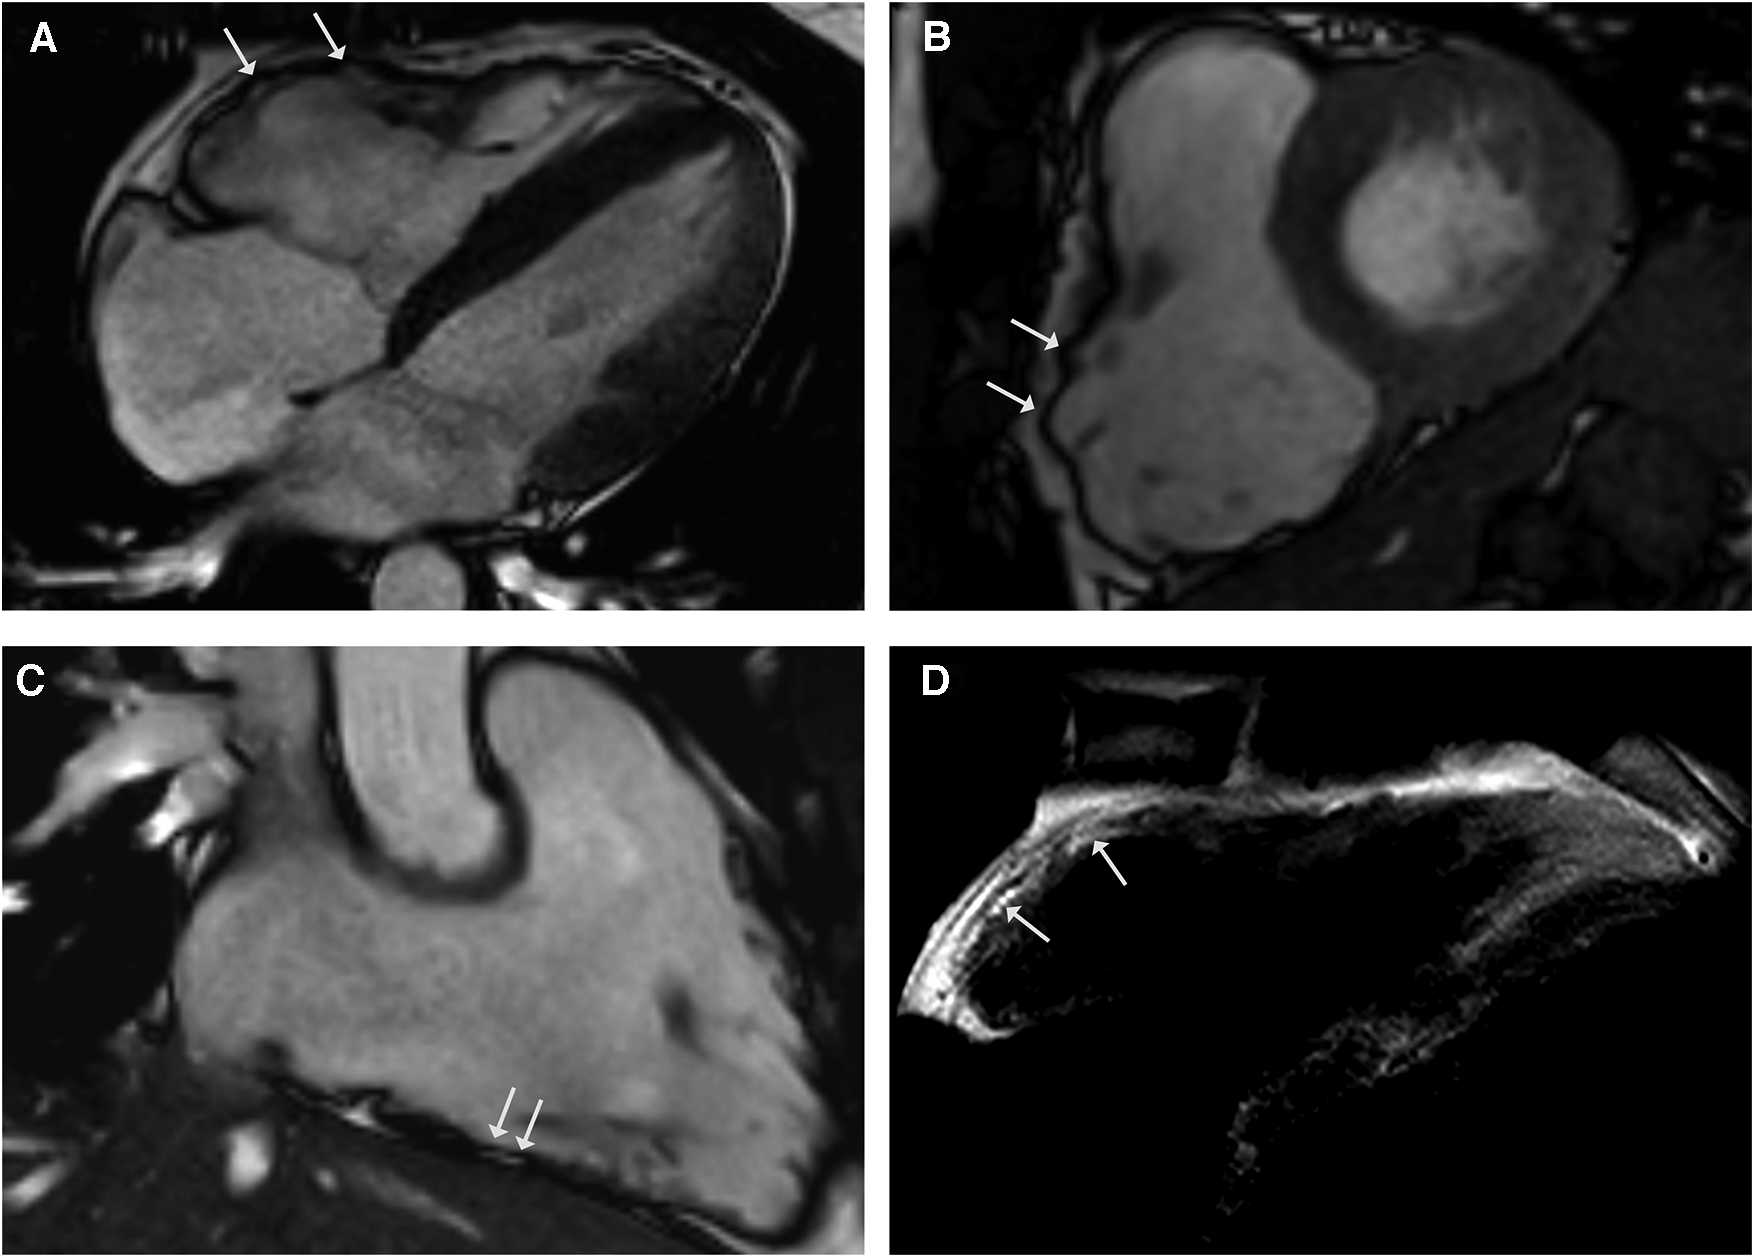

Case 4: sarcoidosis and ACM

A 28-year-old male athlete with a history of exercise-induced syncope presented at our clinic. He reported palpitations and loss of consciousness during intensive physical activity as an American football player. His family history was negative for sudden cardiac death. The clinical examination, blood testing, and 12-lead ECG were unremarkable. The transthoracic echocardiogram showed right ventricular enlargement without dyskinesia. Exercise testing and signal-averaged ECG were normal. The CMR revealed a dilated right ventricle with regional dyssynchrony and moderately decreased right ventricular ejection fraction of 42% (Figures 4A–D). The RV end-diastolic volume index was measured at 130 ml/m2. Despite the strong recommendation against competitive sports, he suffered a cardiac arrest during training, with ECG showing ventricular fibrillation. Immediate defibrillation failed, and he was transferred to our institution under ongoing cardiopulmonary resuscitation. Sinus rhythm was restored post-ECMO, but the patient died due to cerebral edema. The postmortem genetic testing identified a novel pathogenic mutation in plakophilin-2 (PKP2), leading to premature truncation (NM_004572.3 c.1540_1543delAAAC). The autopsy confirmed ACM, and extracardiac sarcoidosis was found in multiple organs including the lungs, pleura, spleen, liver, lymph nodes, and pelvis. Notably, there was no evidence of cardiac involvement in the samples examined.

Figure 4

CMR cine images in 4-chamber (A) and short-axis - views (B) revealing right ventricular dilatation with bulging (arrows) and regional dyssynchrony in end-systolic phase. Right ventricular systolic function was mildly reduced (RV EF 42%). CMR 3-chamber view of the RV (C) demonstrating fatty spots. (D) T1-weighted black blood spin CMR showing fatty replacement of the RV free wall.